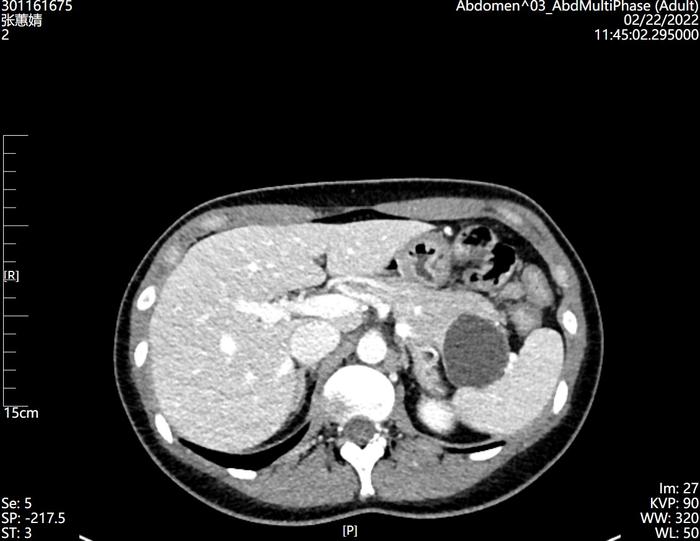

胰腺癌,一般指胰腺导管上皮腺癌(PDAC),好发于中老年人,临床上可以有新发糖尿病、背痛、黄疸等表现,影像学特点是乏血供肿块伴有胰管扩张、胰腺实质萎缩,容易侵犯胰腺周围血管,恶性程度高、预后差,有特异性肿瘤标记物Ca199。病理特点可以胰腺组织内基本结构被破坏,异型腺体浸润性生长,侵犯神经,间质纤维组织增生。尽可能早发现早手术(但是太难了),如不能手术,则应通过辅助化疗或放化疗结合降期,以达到手术时机。?